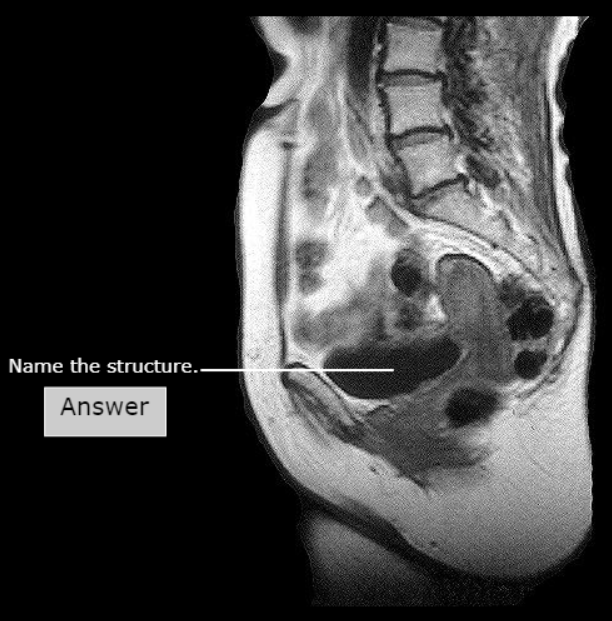

Pubic Symphysis

Cervix

Body of Uterus

Rectouterine Pouch (Pouch of Douglas)

Cervix of the Uterus, Vagina

Posterior Fornix

Fundus of Uterus